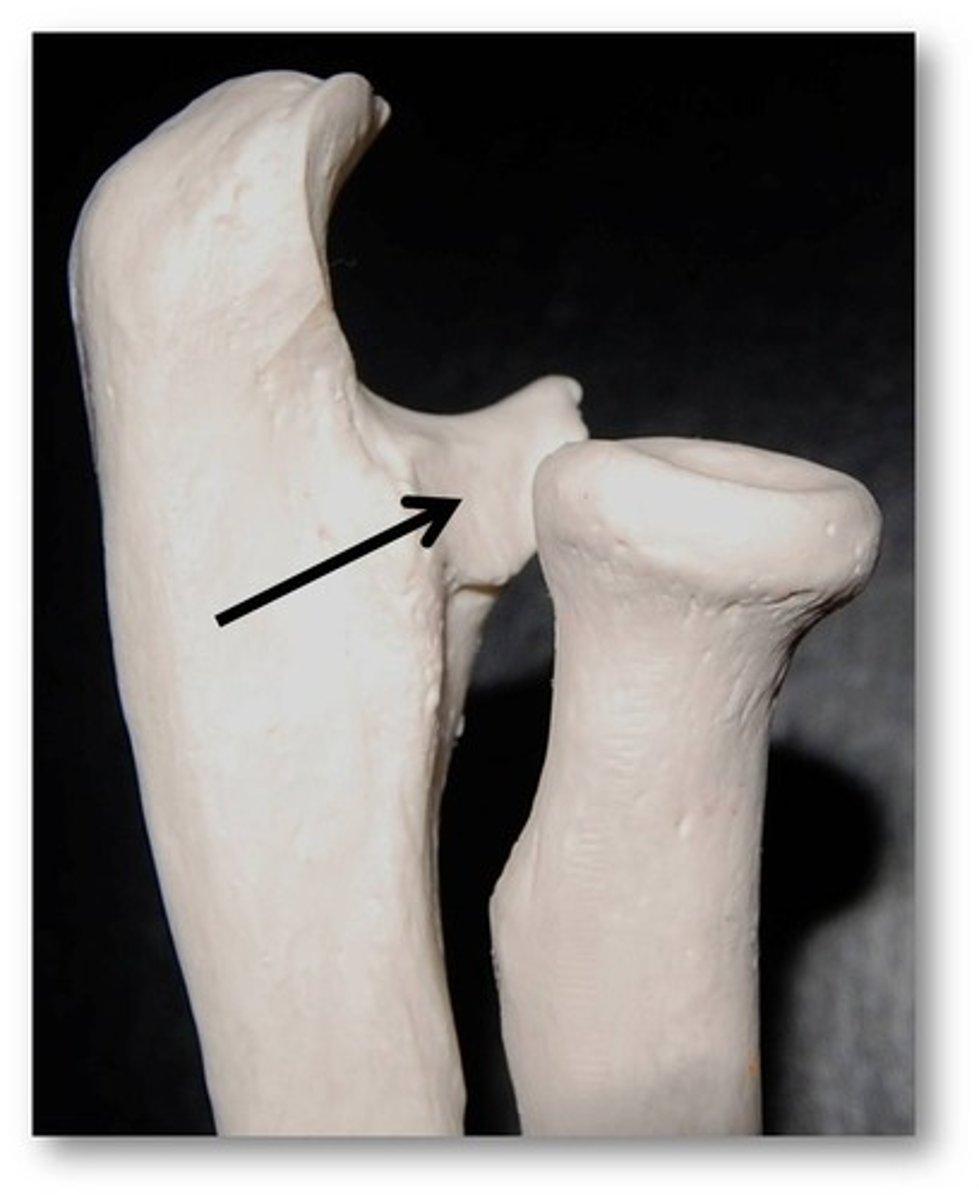

Greater trochanter

Name this specific part of the femur.

Greater trochanter

Name this specific part of the femur.

Head

Name this specific part of the femur.

Neck

Name this specific part of the femur.

Neck

Name this specific part of the femur.